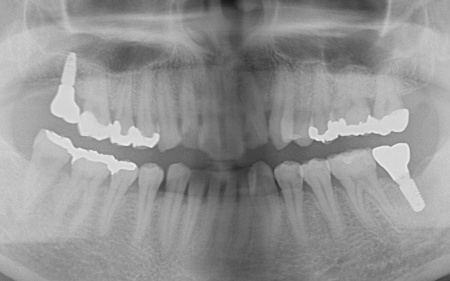

拝見したところ、複数の歯に虫歯が見られました。また、過去に治療した詰め物や被せ物が合わなくなっている部分や、歯が欠損している部位もあります。

一番奥の歯が欠損し、その手前の歯は詰め物の内部で虫歯が進行しています。

噛む面や歯間に虫歯が見られ、歯が欠けている部分もあります。

一番奥の歯は、詰め物が合っていませんでした。また、詰め物が外れたままの歯もあります。

一番奥の歯は虫歯が深くまで進行しており、歯の温存が難しい状態でした。さらに、その手前の歯2本は少し欠けています。

・インプラント治療

保存が難しい左下奥歯(第2大臼歯)と、すでに欠損していた右上の部位については、インプラント治療を行います。インプラント治療とは、顎の骨に人工歯根を埋め込み、そこに人工歯を取り付ける治療方法です。

まず、保存が難しい左下奥歯(第2大臼歯)を抜きます。抜歯後は骨が治癒するまで経過観察を行い、治癒したことを確認後、インプラントの埋入手術を行いました。

右上の欠損部位についても、同じくインプラント治療を実施しています。